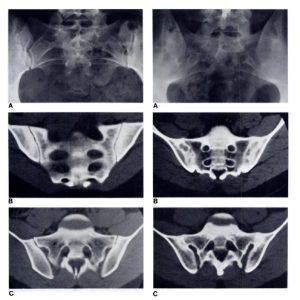

4.1 Chẩn đoán hình ảnh

Các kỹ thuật chẩn đoán hình ảnh đóng vai trò quan trọng trong xác định viêm khớp cùng chậu.

- X-quang giúp phát hiện thay đổi ở khớp cùng chậu trong giai đoạn muộn như xơ hóa, hẹp khe khớp.

- MRI (Cộng hưởng từ) là tiêu chuẩn vàng, có thể phát hiện sớm tình trạng viêm hoặc phù xương.

- CT Scan được dùng để quan sát chi tiết cấu trúc xương, giúp loại trừ nguyên nhân khác như gãy hoặc u xương.

Hình ảnh X-Quang viêm khớp cùng chậu qua từng giai đoạn

(Nguồn: ECO Pharma)